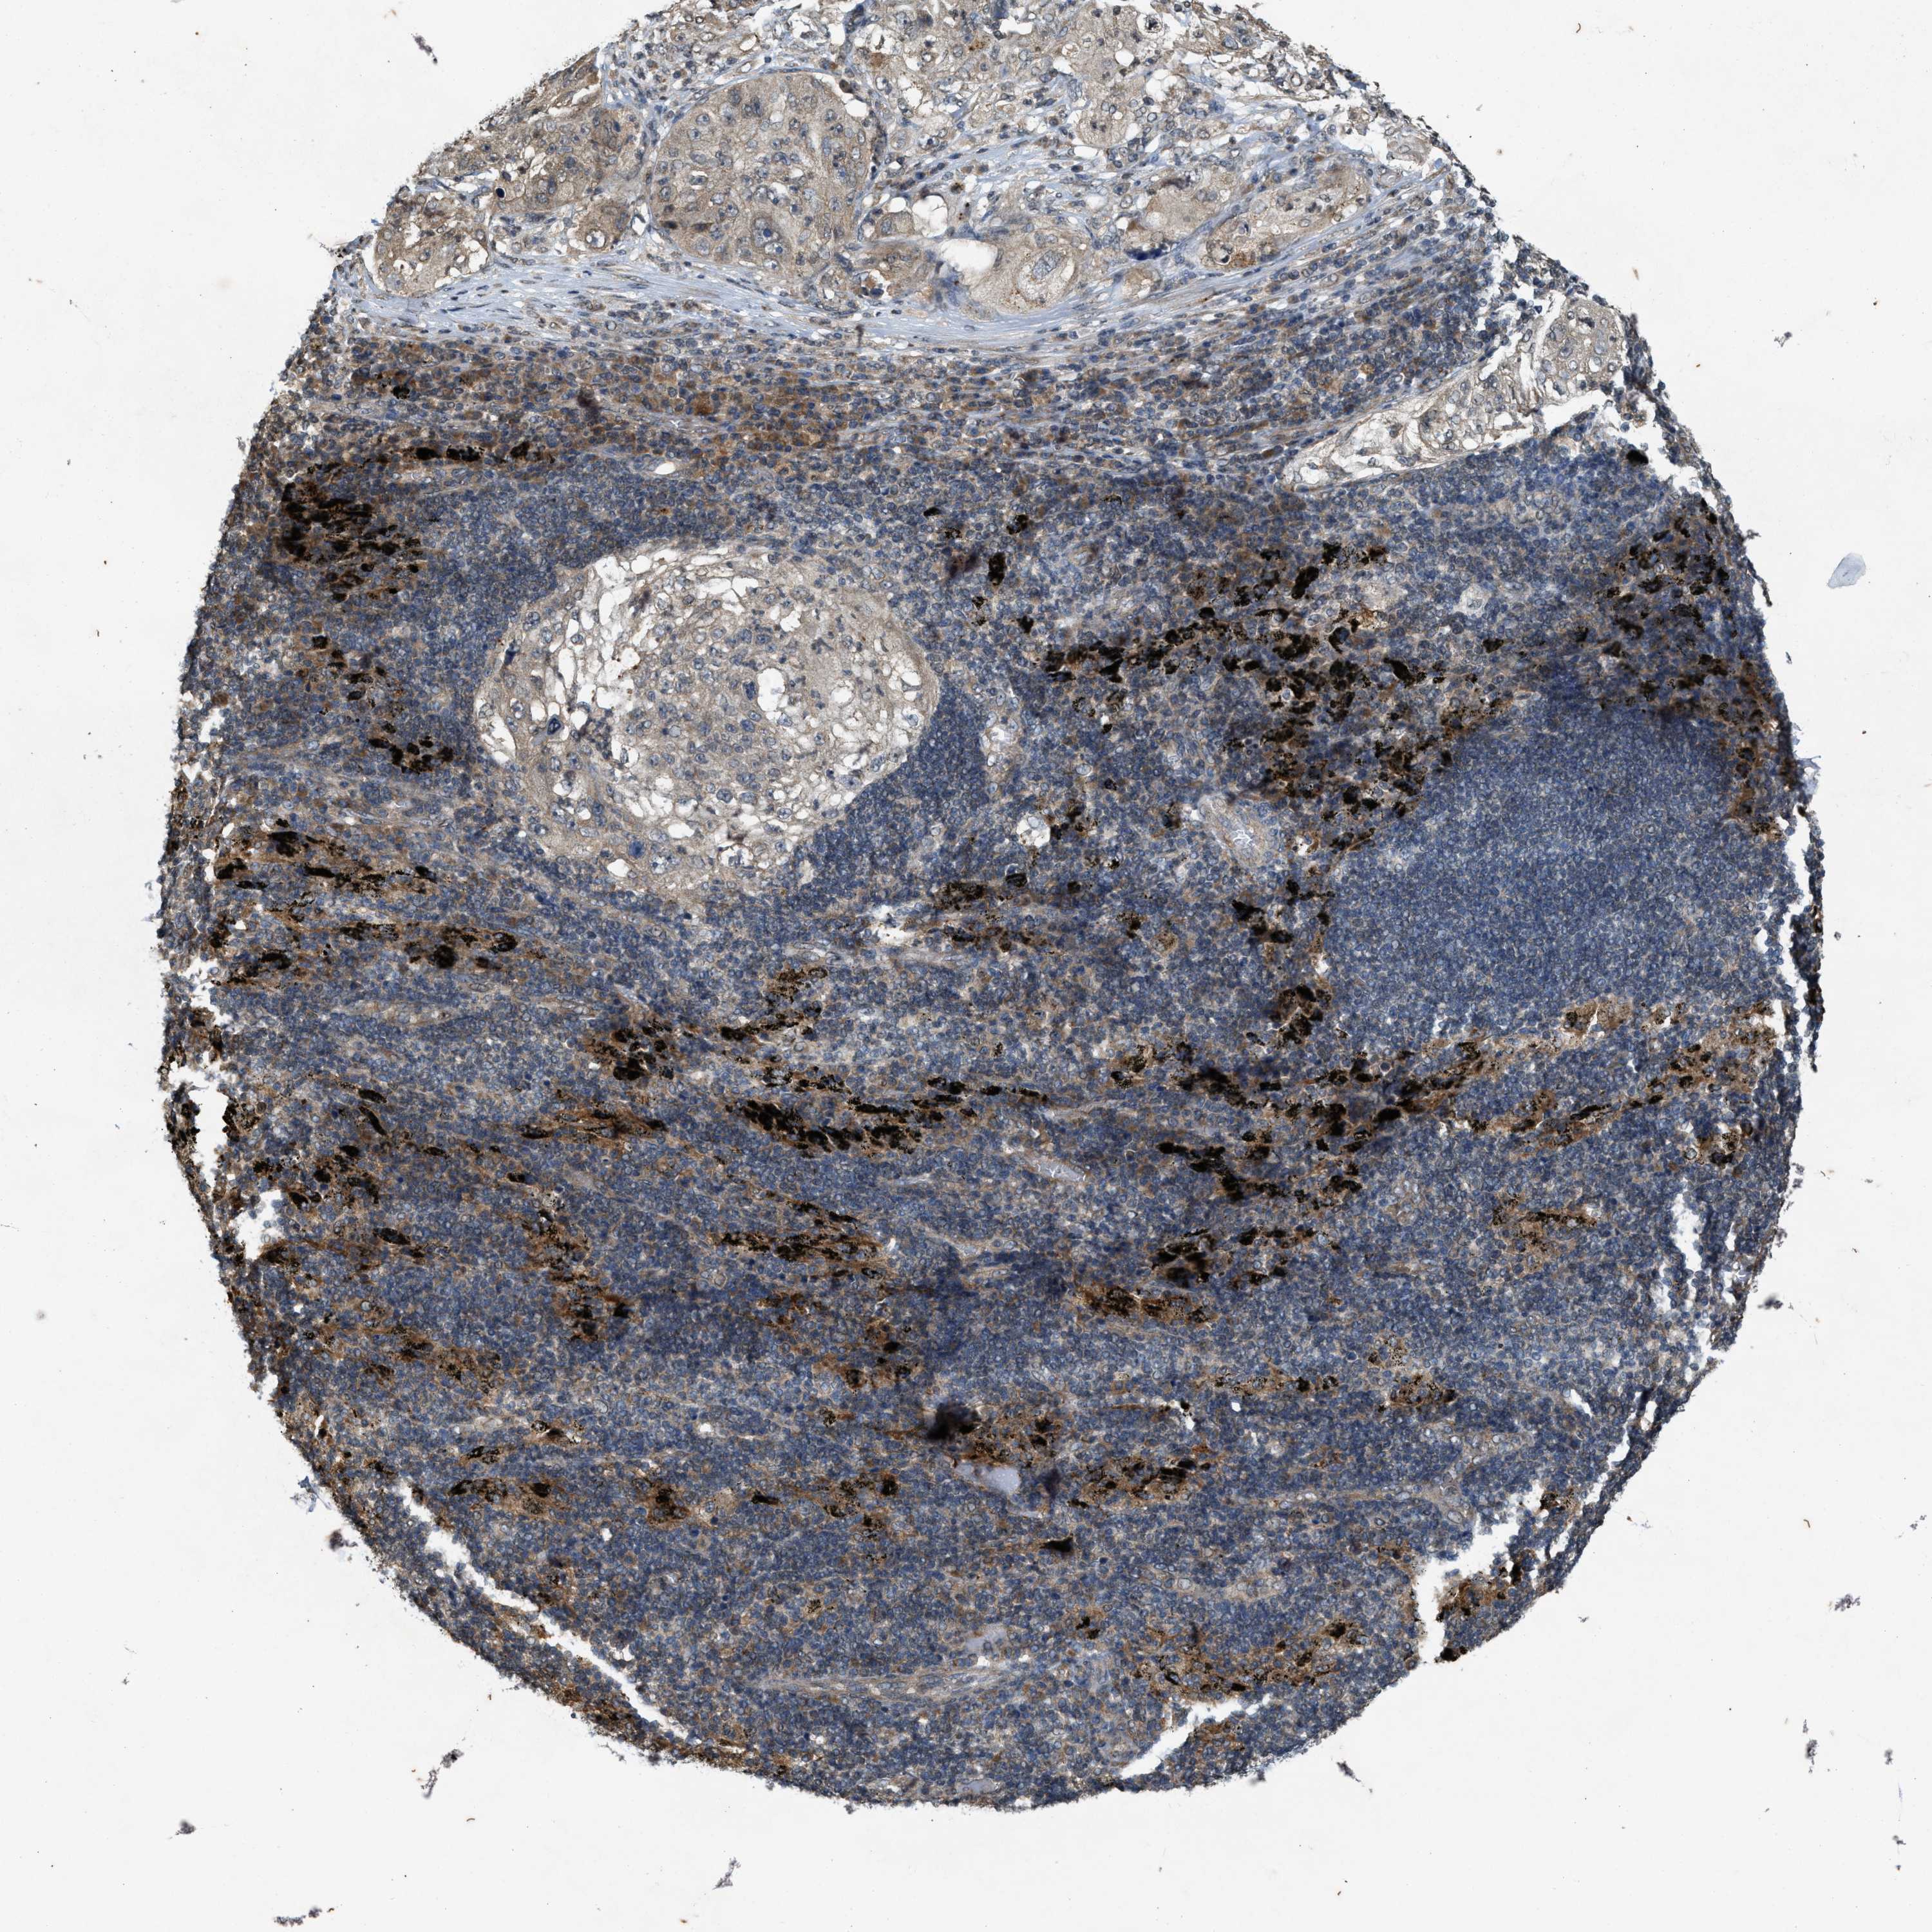

LUNG SQUAMOUS CELL CARCINOMA (TCGA) - Interactive survival scatter ploti

The Survival Scatter plot shows the clinical status (i.e. dead or alive) for all individuals in the patient cohort, based on the same data that underlies the corresponding Kaplan-Meier plots. Patients that are alive at last time for follow-up are shown in blue and patients who have died during the study are shown in red.

The x-axis shows the expression levels (FPKM) of the investigated gene in the tumor tissue at the time of diagnosis. The y-axis shows the follow-up time after diagnosis (years). Both axes are complimented with kernel density curves demonstrating the data density over the axes. The top density plot shows the expression levels (FPKM) distribution among dead (red) and alive patients (blue). The right density plot shows the data density of the survived years of dead patients with high and low expression levels respectively, stratified using the cutoff indicated by the vertical dashed line through the Survival Scatter plot. This cutoff is automatically defined based on the FPKM cutoff that minimizes the p-score. The cutoff can be changed by dragging the vertical line or by entering a cutoff value in the square labeled "Current cut-off".

Under the Survival Scatter plot the p-score landscape (black curve; left axis) is shown together with dead median separation (red curve; right axis). Dead median separation is the difference in median mRNA expression between patients who have died with high and low expression, respectively. It is calculated as follows: median FPKM expression of dead patients with high expression - median FPKM expression of dead patients with low expression. This is intended to aid the user in visually exploring custom cutoffs and the associated p-scores and dead median separation.

Individual patient data is displayed and can be filtered by clicking on one or more of the category buttons on the top of the page. Categories describing expression level and patient information include: high, low, alive, dead, female, male and tumor stages. The scale of the x-axis can be toggled between linear and log-scale by clicking on the "x log" button. Mouse-over function shows TCGA ID, patient information and mRNA expression (FPKM) for each patient.

& Survival analysisi

Kaplan-Meier plots summarize results from analysis of correlation between mRNA expression level and patient survival. Patients were divided based on level of expression into one of the two groups "low" (under cut off) or "high" (over cut off). X-axis shows time for survival (years) and y-axis shows the probability of survival, where 1.0 corresponds to 100 percent.

KIF21A is not prognostic in Lung Squamous Cell Carcinoma (TCGA)

Best expression cut offi

Based on the FPKM value of each gene, patients were classified into two groups and association between prognosis (survival) and gene expression (FPKM) was examined. The best expression cut-off refers the FPKM value that yields maximal difference with regard to survival between the two groups at the lowest log-rank P-value. Best expression cut-off was selected based on survival analysis .

When clicking on this number, the vertical dashed line indicating cut-off, the interactive survival plot, and the Kaplan-Meier curve will be adjusted to show results based on the best expression cut-off.

: 9.04

Median expressioni

P scorei

Log-rank P value for Kaplan-Meier plot showing results from analysis of correlation between mRNA expression level and patient survival.

N/A

TCGA RNA samplesi

RNA-seq data is reported as average FPKM (number Fragments Per Kilobase of exon per Million reads), generated by the The Cancer Genome Atlas (TCGA) .

Normal distribution across the dataset is visualized with box plots, shown as median and 25th and 75th percentiles. Points are displayed as outliers if they are above or below 1.5 times the interquartile range. FPKM values of the individual samples are presented next to the box plot.

Average pTPM 15.0

Number of samples 489